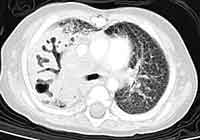

Below are CHEST CT results.

this CHEST CT.

WHAT

IS YOUR INTERPRETATION FOR THE CHEST CT?